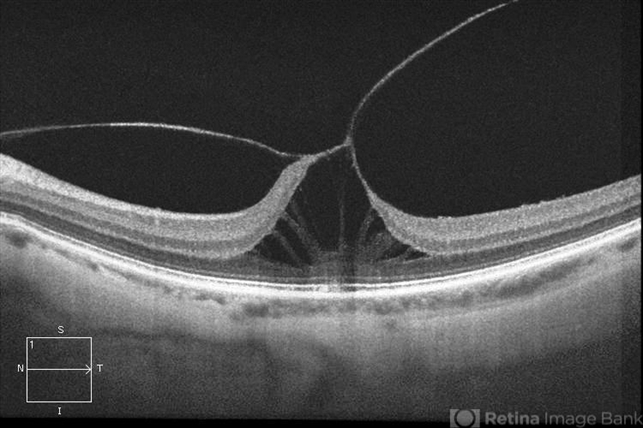

- Symptomatic Vitreomacular Traction

- macular traction

- Optical coherence tomography system

- Patient in with loss of light reflection to the left eye. HD-OCT shows symptomatic vitreomacular traction to the left eye. Patient was injected with Jetrea and will be seen back in 2-weeks for follow-up.